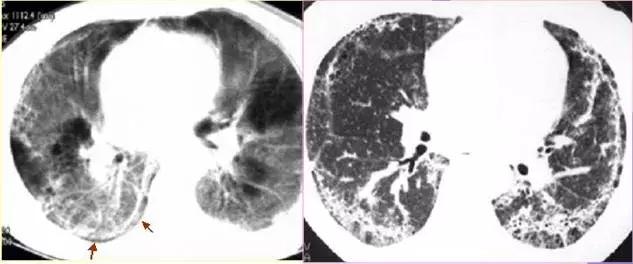

CT征象十:肺间质征与蜂窝肺

胸膜下线表现为:在胸膜下1cm之内,与胸膜走行平行,厚约几mm,长约数cm的弧形细线影,多见于肺间质纤维化等病变中。

小叶间隔线……

蜂窝肺表现为:两肺内大小数mm~数cm,壁菲薄的多发呈蜂窝状的透亮影,多见于肺间质纤维化病变的晚期。

肺间质性病变常有肺小叶间隔增厚

间质性肺水肿——肺小叶间隔增厚

肺癌性淋巴管炎HRCT表现及镜下病理所见

肺间质纤维化——胸膜下弧线影

肺间质纤维化晚期——两肺蜂窝影

两肺弥漫蜂窝影-肺淋巴管肌瘤病,均为女性